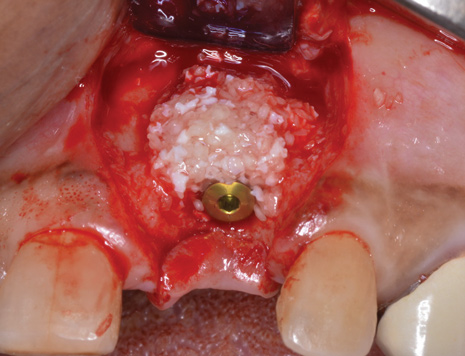

(7.) Because apical and lateral bone volume was preserved with use of an ultrathin trephine, a wider diameter, 4.2-mm implant was placed at the time of implant removal. Bone augmentation was performed, and submerged healing was selected.

Figure 7

(8.) A cross-linked collagen scaffold consisting of FDBA/DBBM in a 4:1 ratio is placed over the particulate bone graft.

Figure 8